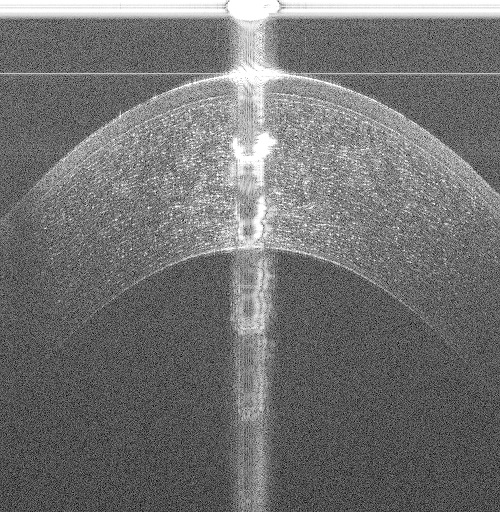

While many non-proprietary image analysis-based corneal interface segmentation approaches exist [6, 7, 8, 9, 10] in literature, they do not generalize to volumes acquired from different OCT scanners. These approaches are ad-hoc with key parameters being chosen manually; for example in Fig. 1, recent approaches [6, 7, 10], developed for images (B-scans) acquired by a Spectral Domain OCT (SD-OCT) scanner scanning a 66mm area, failed while segmenting the Epithelium (shallowest layer) in 33mm volumes acquired by a Ultra High Resolution OCT (UHR-OCT) scanner. Assumptions on the central artifact location [6, 7, 8, 9, 10] break down when they are located in different regions of the image (see Fig. 1(c)). As shown in Figs. 1(a) to 1(c), a segmentation approach must perform reliably across datasets acquired with different scan settings from different scanners, even in the presence of strong vertical and horizontal specular artifacts.

(a)

(b)

(c)